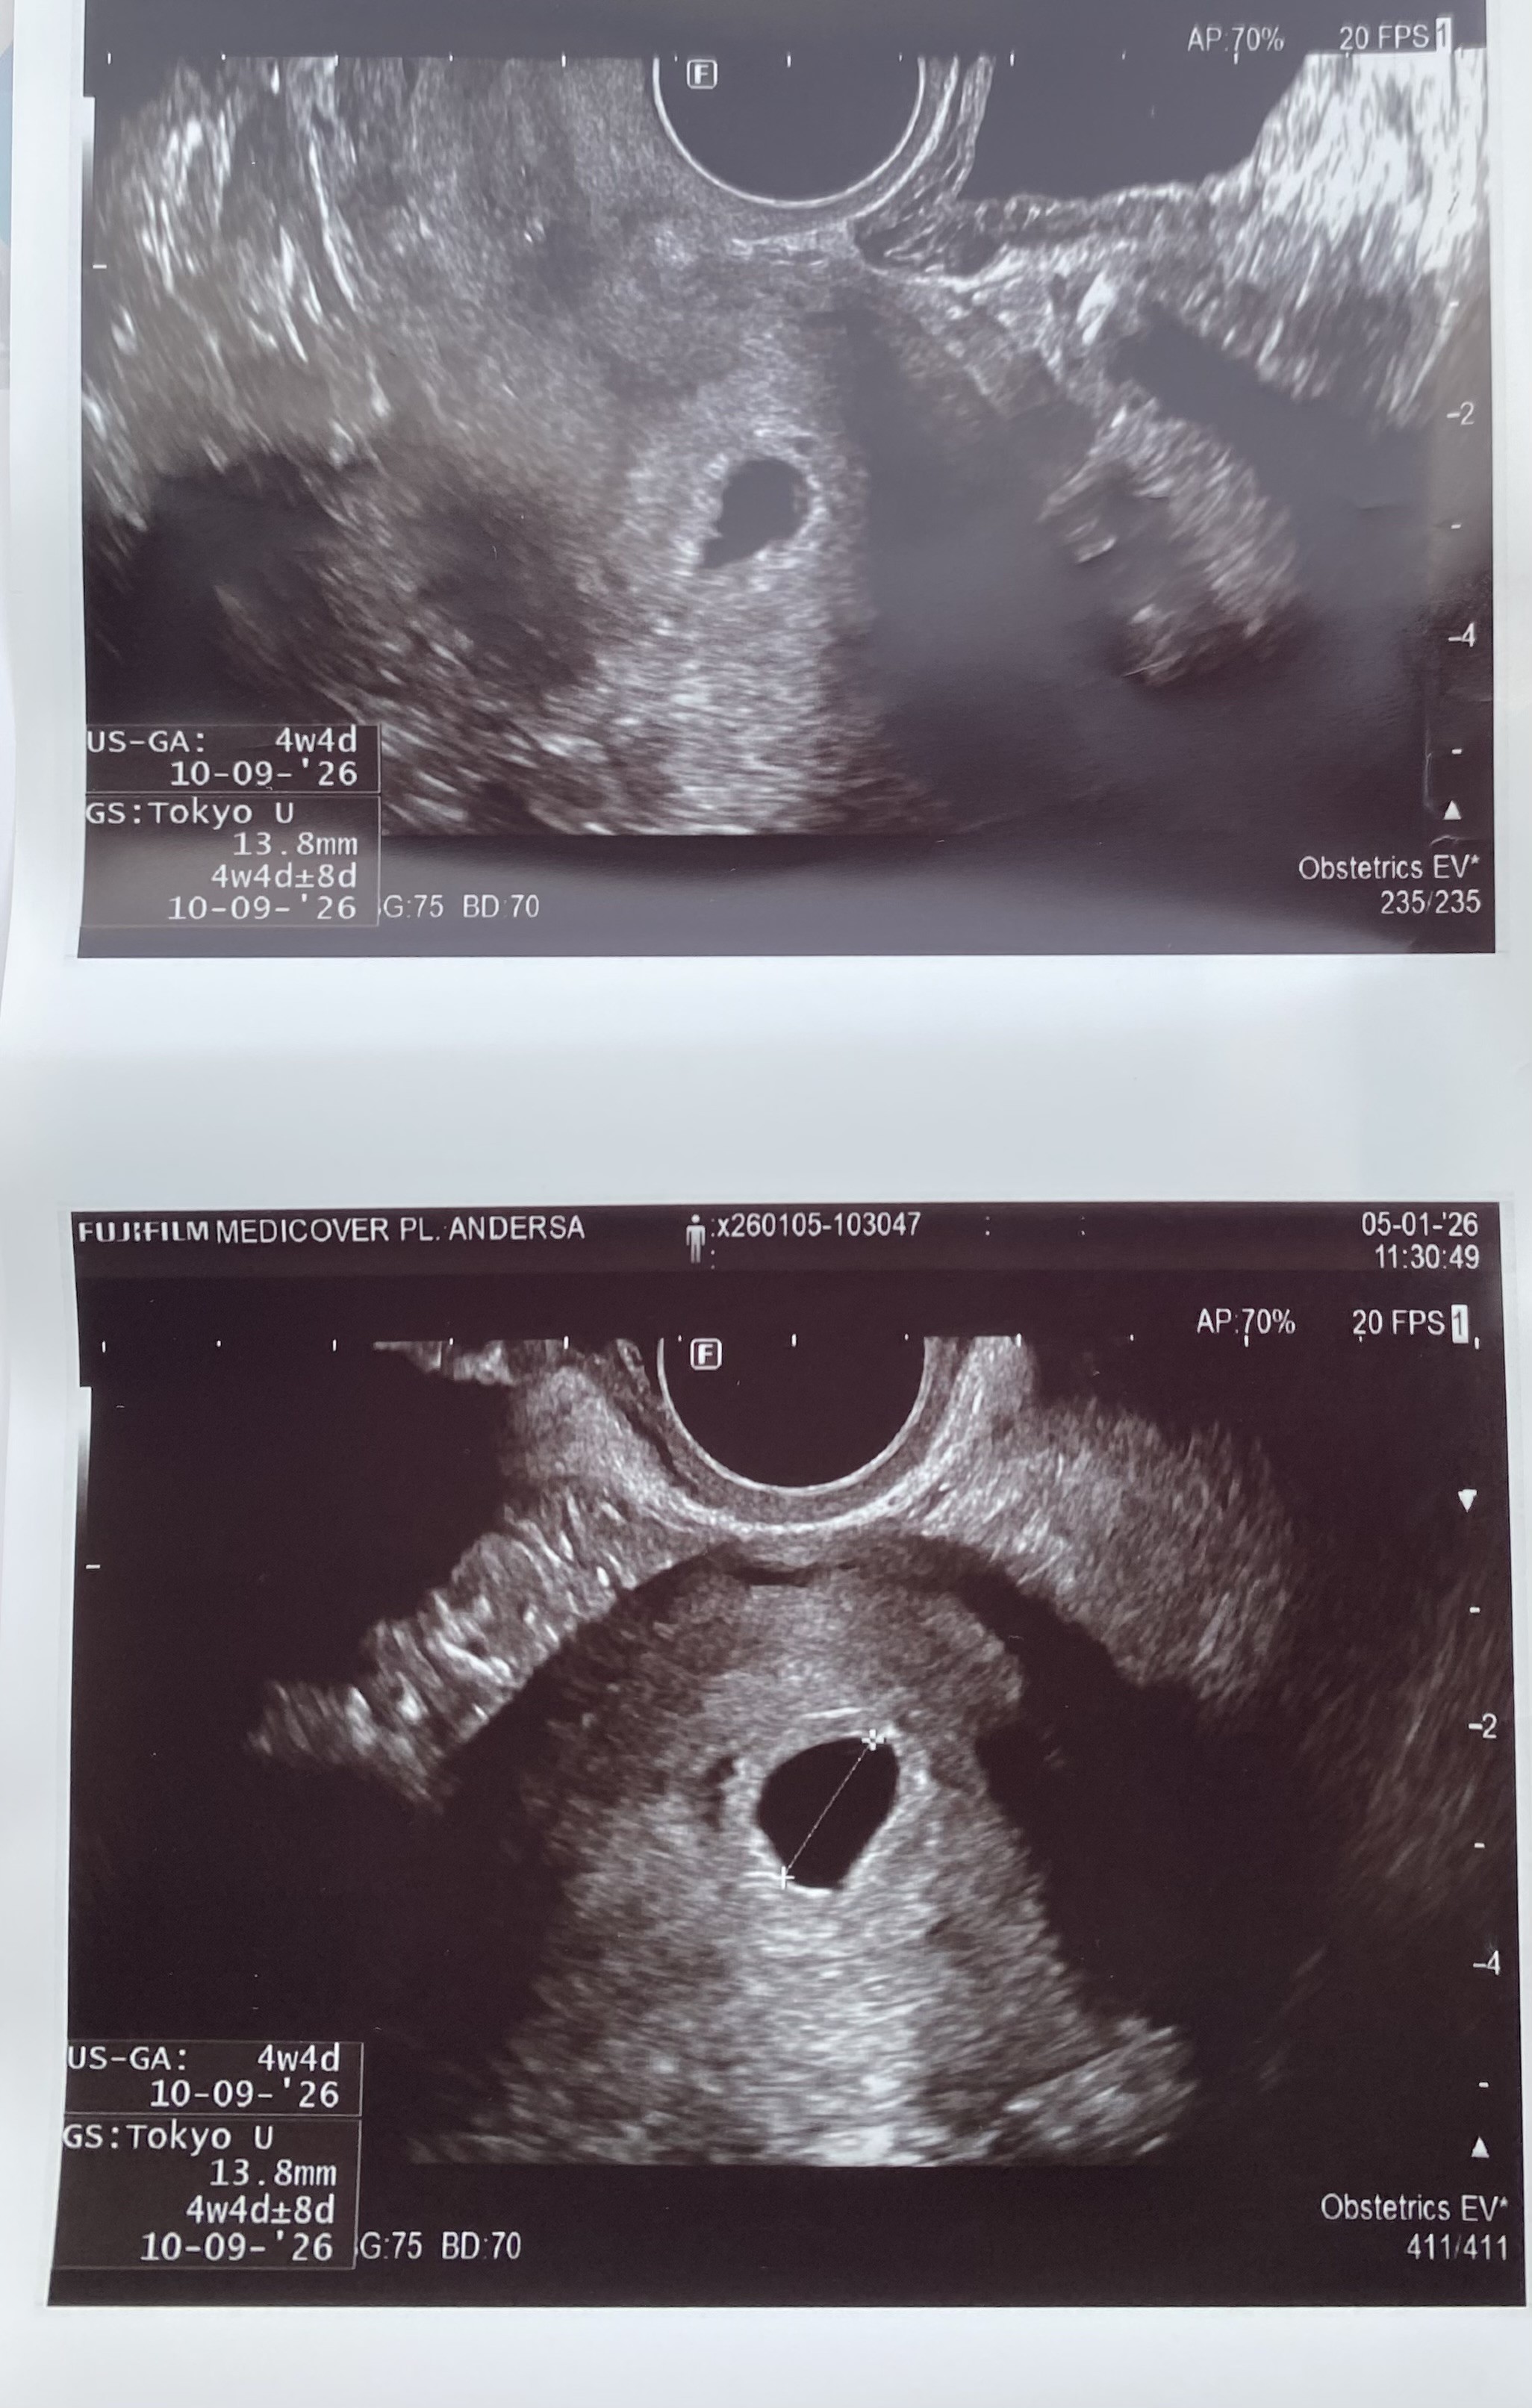

Pęcherzyk ciążowy

Witam, pytanie dotyczy pęcherzyka ciążowego. A mianowicie widać pęcherzyk ale nie widać w nim zarodka i troszkę mnie to martwi😢 Czy możliwe, że jeszcze go nie widać czy może pęcherzyk jest pusty?

• IMG_1584.jpeg

IMG_1584.jpeg

838,3 KB · Wyświetleń: 186